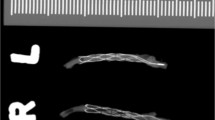

After blood incubation, the exposed tubes were washed using saline and stained with hematoxylin (0.1%) for 30 min. The fibrin deposition on the tubes was photographed and evaluated using ImageJ in order to assess the degree of fibrin coverage formed during the exposure (Supplementary Fig. 1).

A correlation was observed between high levels of TAT generation and increased fibrin deposition on the tubes exposed to both pig and human blood. The lower TAT values in the coated groups showed minimal fibrin coverage (Fig. 4). Significance based on paired t-test of the coated and control group (n = 20).